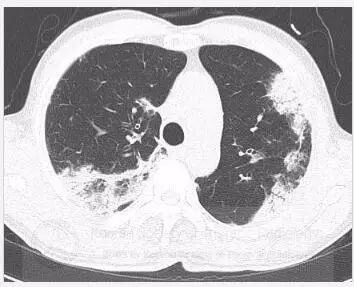

初始胸片显示双肺斑片状或外周实变,以及磨玻璃影。胸部CT显示双肺多灶性、斑片状实变,伴中央空气支气管征,以及外周磨玻璃影。病变在外周、上叶多见。

使用糖皮质激素治疗,3个月后病灶几乎消失。

胸片常显示不呈段或叶性分布的周围片状阴影,常为双侧分布。CT显示典型的不呈段性气腔实变,以外周受累为主。不常见表现包括磨玻璃影、结节和网格影。